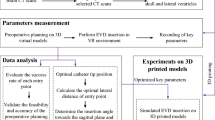

2.4 Statistical analysis

Continuous variables were summarized using means, while categorical variables were presented as counts and percentages. The accuracy of freehand insertion using AR guidance was reported either as means or percentages, extracted directly from the studies or calculated based on reported outcomes. To visualize the average accuracy of each study forest plots were used, indicating the range where 95% of the observed accuracies lie (two standard deviations from the mean). The Kruskal-Wallis test was used to analyze the variance of accuracy for the different devices. A p value lower than 0.05 was deemed significant. All statistical analyses were performed using the statistical software R (R Foundation for Statistical Computing, Vienna, Austria).

The 11 Studies reporting the deviation from the planned path revealed an average accuracy ranging between 0.7 to 11.9 mm (Fig. 2). Insertions performed by neurosurgeons consistently exhibited higher accuracy with deviations below 5.2 mm. There were no significant differences (p = 0.755) in accuracy for the different interfaces: Microsoft HoloLens (HMD), ARSN (External monitor), and tablet screens. The type of subject experimented on did not yield significant variations in accuracy. The study by Li et al. (2018) including neurosurgeons and a control group, investigating bedside placement of EVD on patients, demonstrated a significant improvement in accuracy. The average deviation from target decreased from 11.3 to 4.3 mm.

Reported average accuracy from each study with respective 95% interval. Studies that did not report accuracy in means were excluded in this plot. Dotted line marks 5 mm. Grey circles: average accuracy of AR-guided EVD insertion. Black squares: accuracy achieved by control groups performing freehand insertions

The studies by Van Gestel et al. (2021) and Eom et al. (2022), involved medical students using Microsoft HoloLens. Both studies had control groups using the freehand technique. Compared to these control groups, the use of Microsoft HoloLens improved accuracy. The deviations decreased from 19.9 to 11.9 mm, and from 13.5 to 7.4 mm, in the respective study.

The study by Benmahdjoub et al. (2023) that included students and employees achieved high accuracy for both AR devices (Xiaomi tablet and Microsoft HoloLens), both exhibiting an average deviation of 2 mm. The study by Bounajem et al. (2023) which included medical students, clinicians, and engineers using Microsoft HoloLens, reported a low average deviation of 1.9 mm.

Studies that used the Kakarla grading system showed AR accuracies, between 82 and 96% (Fig. 3). Among these studies, two conducted comparative analyses between AR-assisted and the freehand technique. In these control groups, the accuracy of EVD insertion was 72% and 73%, respectively. Notably, the study conducted by Schneider et al. (2023) initially indicated that the freehand technique (73%) yielded higher accuracy than AR (68%). However, after undergoing three sessions of training with AR navigation, accuracy significantly improved to 95%. In all three studies, EVD insertions were carried out by neurosurgeons using Microsoft HoloLens. The study conducted by Kunz et al. (2021) was performed on patients, and the other two on anthropomorphic phantoms.

Percentage of accurately placed drains according to the Kakarla grading system. The rate of accurate AR insertion is presented in black. The accuracy reported by control groups using the freehand technique is presented in grey. The study by Umana et al. (2021) lacks a control group